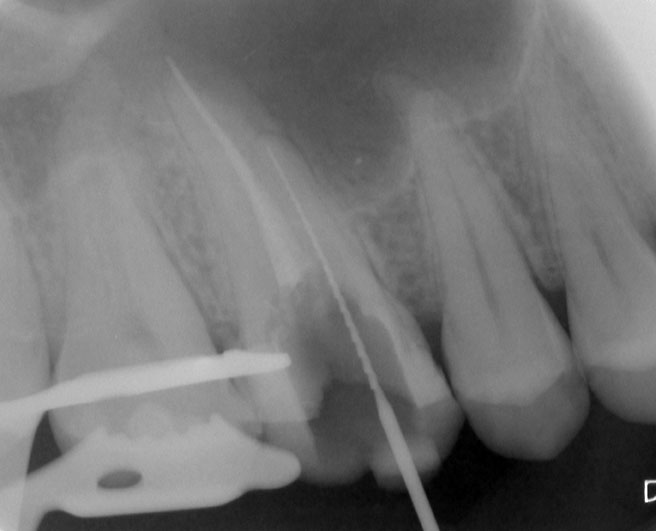

Nach Darstellung aller Wurzelkanaleingänge wird in einem zweiten Schritt das frakturierte Wurzelkanalinstrument dargestellt (Abb. 3 u. 4). Hierfür verwenden wir den Aufsatz 3E des Tigon+. Durch die schmale und lange Form des Instruments erreichen wir einen tiefen und schmalen Zugang.

Sofern es sich um ein kleines Frakturstück handelt, kann es durch aktive Übertragung von Energie des Ultraschalls zu einer Lockerung des Fragments kommen. Lockert es sich nicht, so „umkreist“ man das Instrument vorsichtig, um es anschließend mit einer Spritze gefüllt mit Palavit G zu greifen, zu fixieren und zu entfernen (Abb. 5). Nach Entfernung des Instruments erfolgt eine Kontrollaufnahme (Abb. 6).